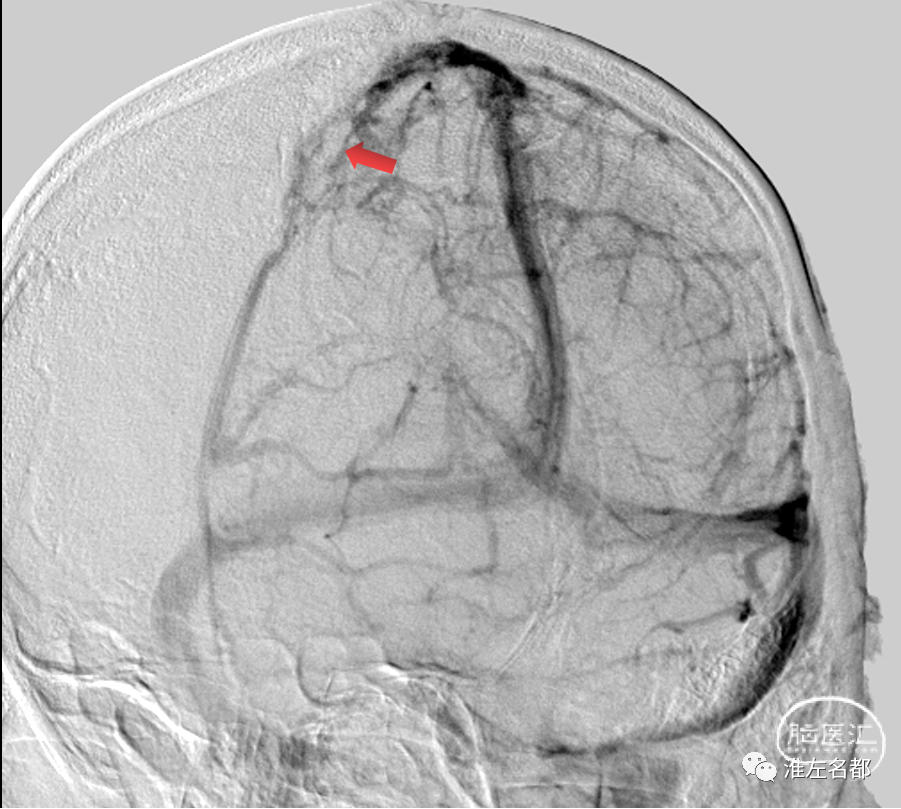

术中DSA:上矢状窦中部血栓充盈缺损(红箭),局部皮质静脉引流不畅。

术中微导管通过上矢状窦血栓造影:血栓位置管腔狭窄,血流通过不畅。

于上矢状窦血栓位置置入取栓支架(S AB 6*30mm)取栓两次,取出多块红色血栓。

取栓术后造影:原血栓部位管腔较前明显改善,局部皮质静脉引流也改善。